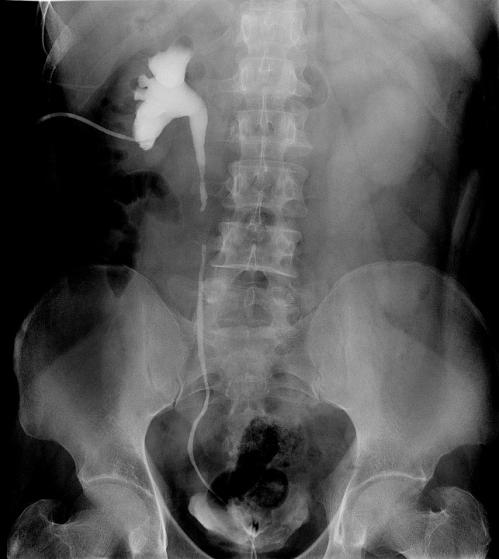

近日,一例在外院行输尿管镜钬激光碎石术后肾积水加重的患者,术前顺行+逆行造影确定输尿管狭窄程度及长度(见图1),经过术前精心准备和科室讨论,我科席启林主任医师决定为患者施行颊粘膜自体移植术,经腹全腹腔镜下修复右输尿管上段长段狭窄(onlay graft + augmented anastomosis技术,手术顺利,目前患者恢复良好。由于患者肥胖体型(115kg),颈脖短,麻醉科移小峰主任和彭艳主任选择经鼻腔气管插管,方便术中从口腔内面获取颊粘膜。整个手术过程麻醉平稳,苏醒非常满意,避免呛咳导致口腔伤口渗血。在口腔科李卫东主任的指导下,汤晶医生克服侧卧位及操作空间非常有限的困难,非常顺利获取了所需大小的颊粘膜。本次手术需要三种不同体位,手术室王堃老师和张维倩老师经验非常丰富,极大满足了手术暴露需要。在此,感谢参与此次手术的相关各科室老师的智慧和辛勤无私的付出!同时,本手术在前期准备过程中得到了上海六院胡晓勇教授和北大泌尿外科研究所李学松教授的悉心指导,在此致谢!

图1 术前造影确定输尿管狭窄